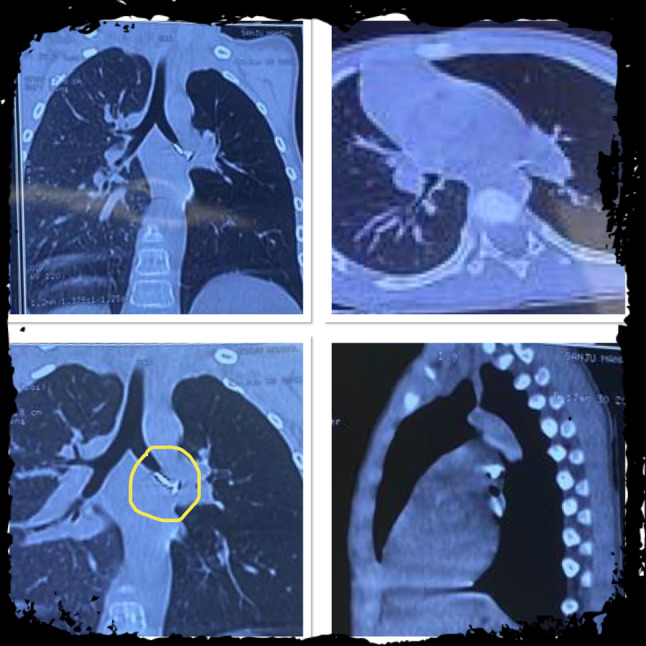

Fig. 5.

Left main bronchus metallic Foreign Body (nail) seen on a CT scan of thorax